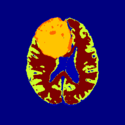

Physiological Brain Activity Longitudinal Study

- Collaborator: Laura Horky PI (Brigham and Women's Hospital(BWH)), Jon Hainer (BWH), Wendy Plesniak (BWH), Alexander Zaitsev (BWH), Ron Kikinis (BWH) and BWH Division of Nuclear Medicine

- Short description: Evaluate glycolitical brain activity in CSF and White Matter for the patients undergoing chemical therapy courses.

- Image specification: 1.5 Tesla ,Scanner: SIGNA EXCITE / GE MEDICAL SYSTEMS, T1, Axial Scans, TR/TI/TE=500/0/21 ms, pixel_xsize = 0.781251, pixel_ysize = 0.781244, fov = 0.000000, aspect = 7.679990, thick = 5.000000, space = 1.000000

- Used Task: MRI Human Brain Hemisphere